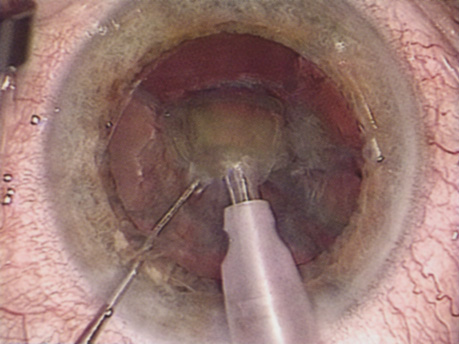

Patients who complain of glare from point sources of light, such as oncoming headlights or bright sunshine, may be best evaluated by a different form of glare testing. To simulate the environment of the patients' symptoms, Snellen acuity is measured while directing a point source of light obliquely toward the eye outside their best spectacle correction or outside of a phoropter dialed in with their best manifest refraction (Fig. 2).